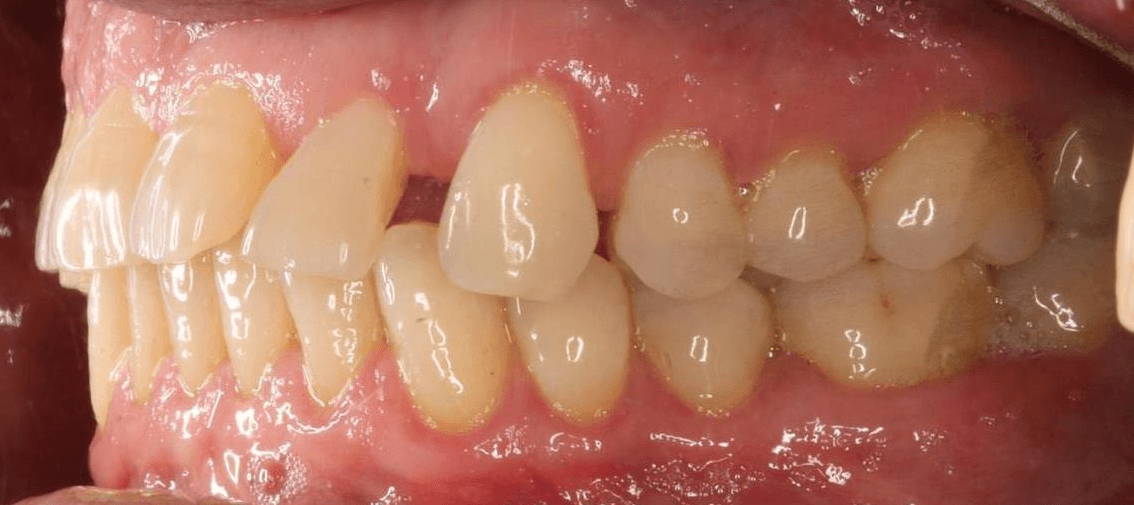

INTRAORAL